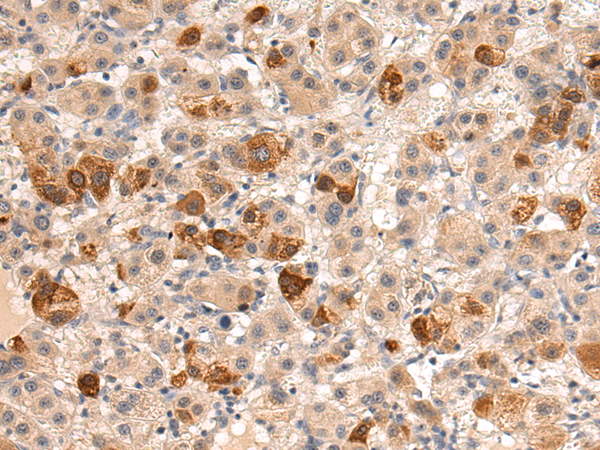

分类: 科研抗体货号: P04011别名: GRM1A, mGlu1, GPRC1A, MGLUR1, SCAR13, MGLUR1A应用: WB,IHC反应种属: Human, Mouse, Rat